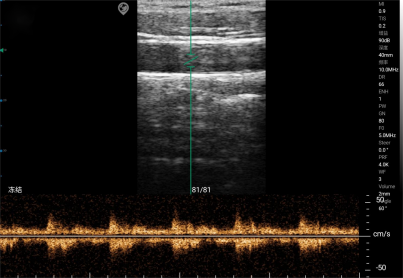

The M-mode displays the intensity of tissue echo signals based on brightness levels, while also showing the movement trajectories of these light spots on the time axis, reflecting one-dimensional tissue structure and motion information.

M-mode ultrasound is primarily employed for the examination of the cardiovascular system, analyzing the motion amplitude of the heart and major blood vessels, dynamically assessing the morphological structure and functional status of the cardiovascular system, and obtaining corresponding physiological or pathological technical indicators of the vessels.